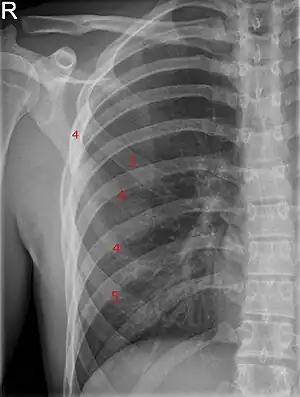

![]() | |

| Bifid rib at the right side seen on chest radiograph. The fourth rib splits in two towards the sternal end. | |

A bifid rib is a congenital abnormality of the rib cage and associated muscles and nerves which occurs in about 1.2% of humans. Bifid ribs occur in up to 8.4% of Samoans.[1] The sternal end of the rib is cleaved into two. It is usually unilateral.

Bifid ribs are usually asymptomatic, and are often discovered incidentally by chest X-ray. Effects of this neuroskeletal anomaly can include respiratory difficulties, neurological difficulties, limitations, and limited energy from the stress of needing to compensate for the neurophysiological difficulties. An unstable bifid rib may lead to slipping rib syndrome.[2]